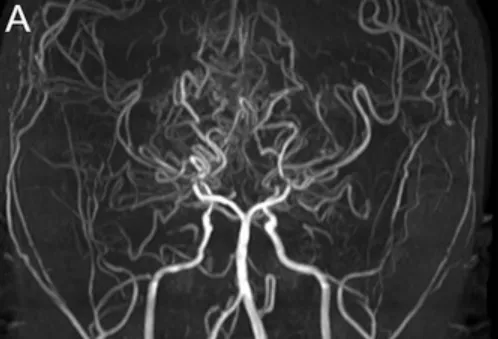

小智第一次就诊时,磁共振血管造影(MRA)显示他双侧颈内动脉、大脑后动脉都有狭窄,属于烟雾病的中晚期(Suzuki 4期)。

MRA和DSA图像显示双侧末端ICA和PCA狭窄(图A)